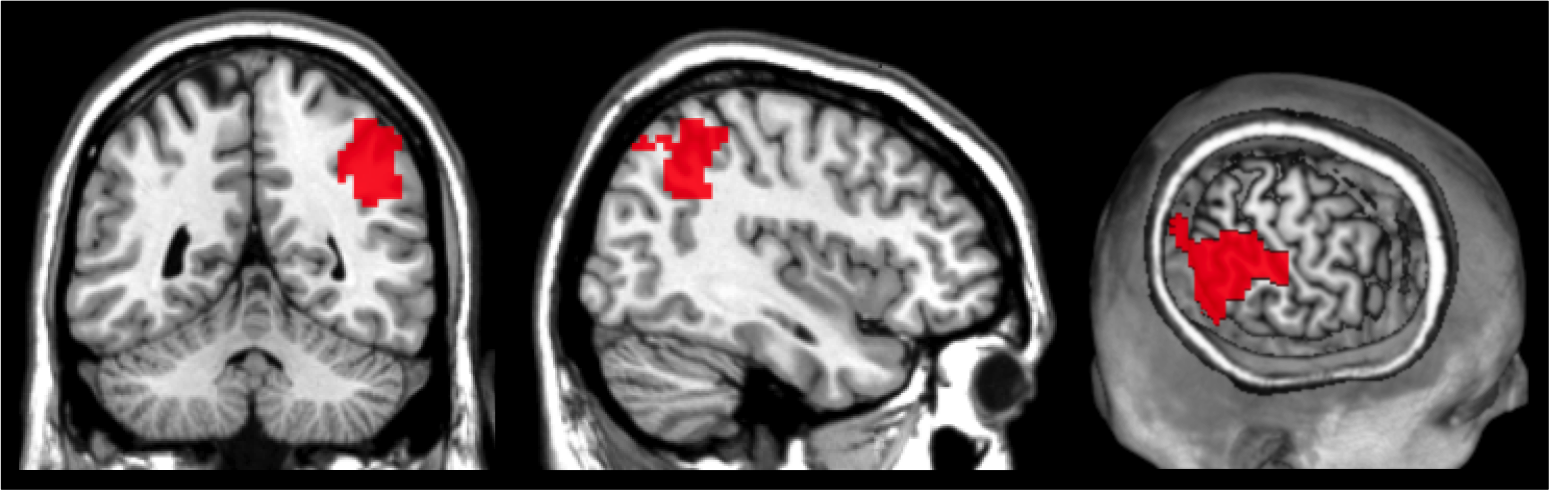

The universities of Düsseldorf and Friedrichshafen use (inter alia) imagine methods, like functional magnetic resonance imaging, are used to analyse the neural underpinnings of decision making.